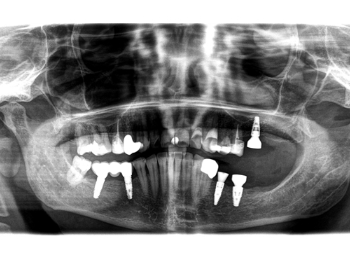

Röntgen OPG Erstbefund

OPG zum Erstbefund.